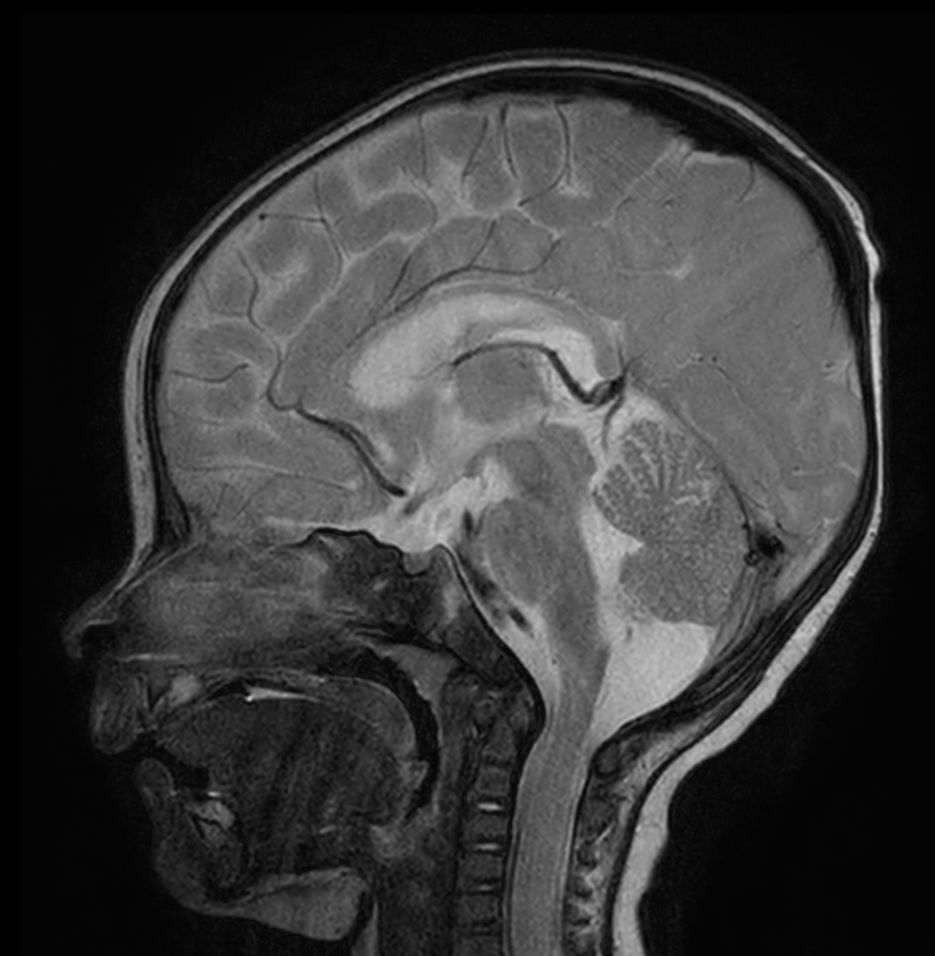

Sagittal T2w TSE with ComforTone

Sagittal 3D T1w TFE with ComforTone

Sagittal 3D T1w TFE with ComforTone (post-gado)